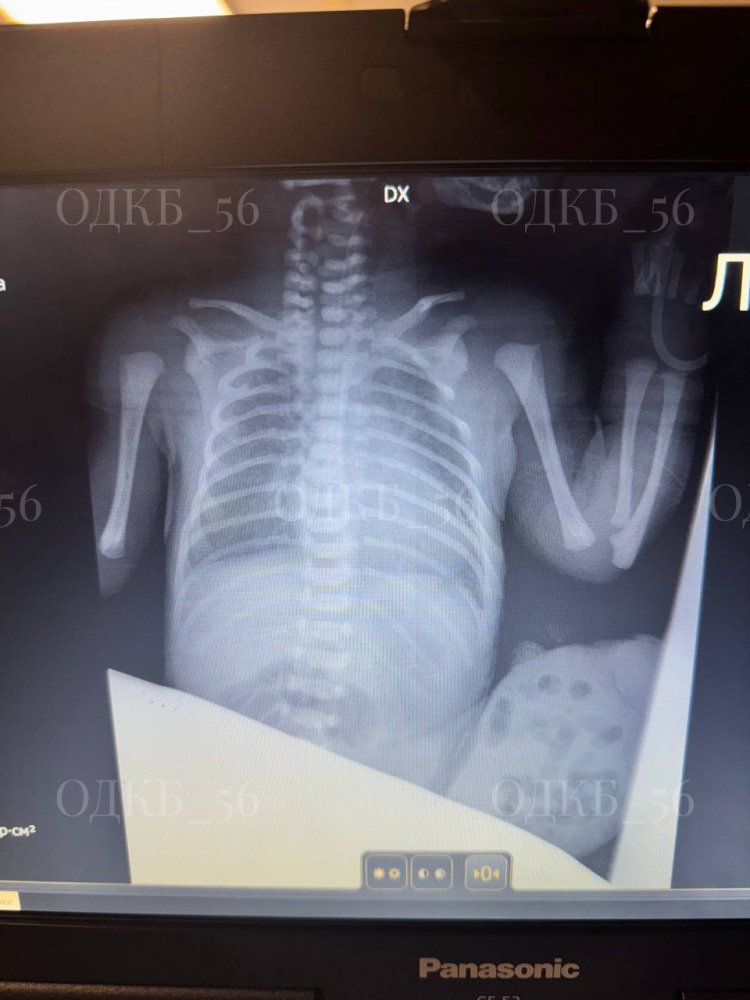

Хирурги областной детской клинической больницы в Оренбурге спасли жизнь новорождённому. Малыш родился с редкой патологией — омфалоцеле (грыжа пупочного канатика) больших размеров. Это врождённый порок, при котором внутренние органы (чаще кишечник, печень) выпячиваются из брюшной полости через пупок в пуповинный остаток. Патология редкая: встречается от 1 до 5 случаев на 10 000 новорожденных.

Сразу после рождения малыша доставили из перинатального центра в Областную детскую клиническую больницу. Врачи приступили к операции: за жизнь малыша боролись зав. детским хирургическим отделением № 1 Андрей Баканов, детский хирург Елена Фролова, анестезиолог-реаниматолог Василий Лазин и операционный медбрат Грачев Вадим. Органы, которые выпячивались, переместили в брюшную полость с учётом их физиологического расположения, сделали пластику, сформировали пупок. Сейчас новорождённый уже в Областном перинатальном центре — рядом с мамой.